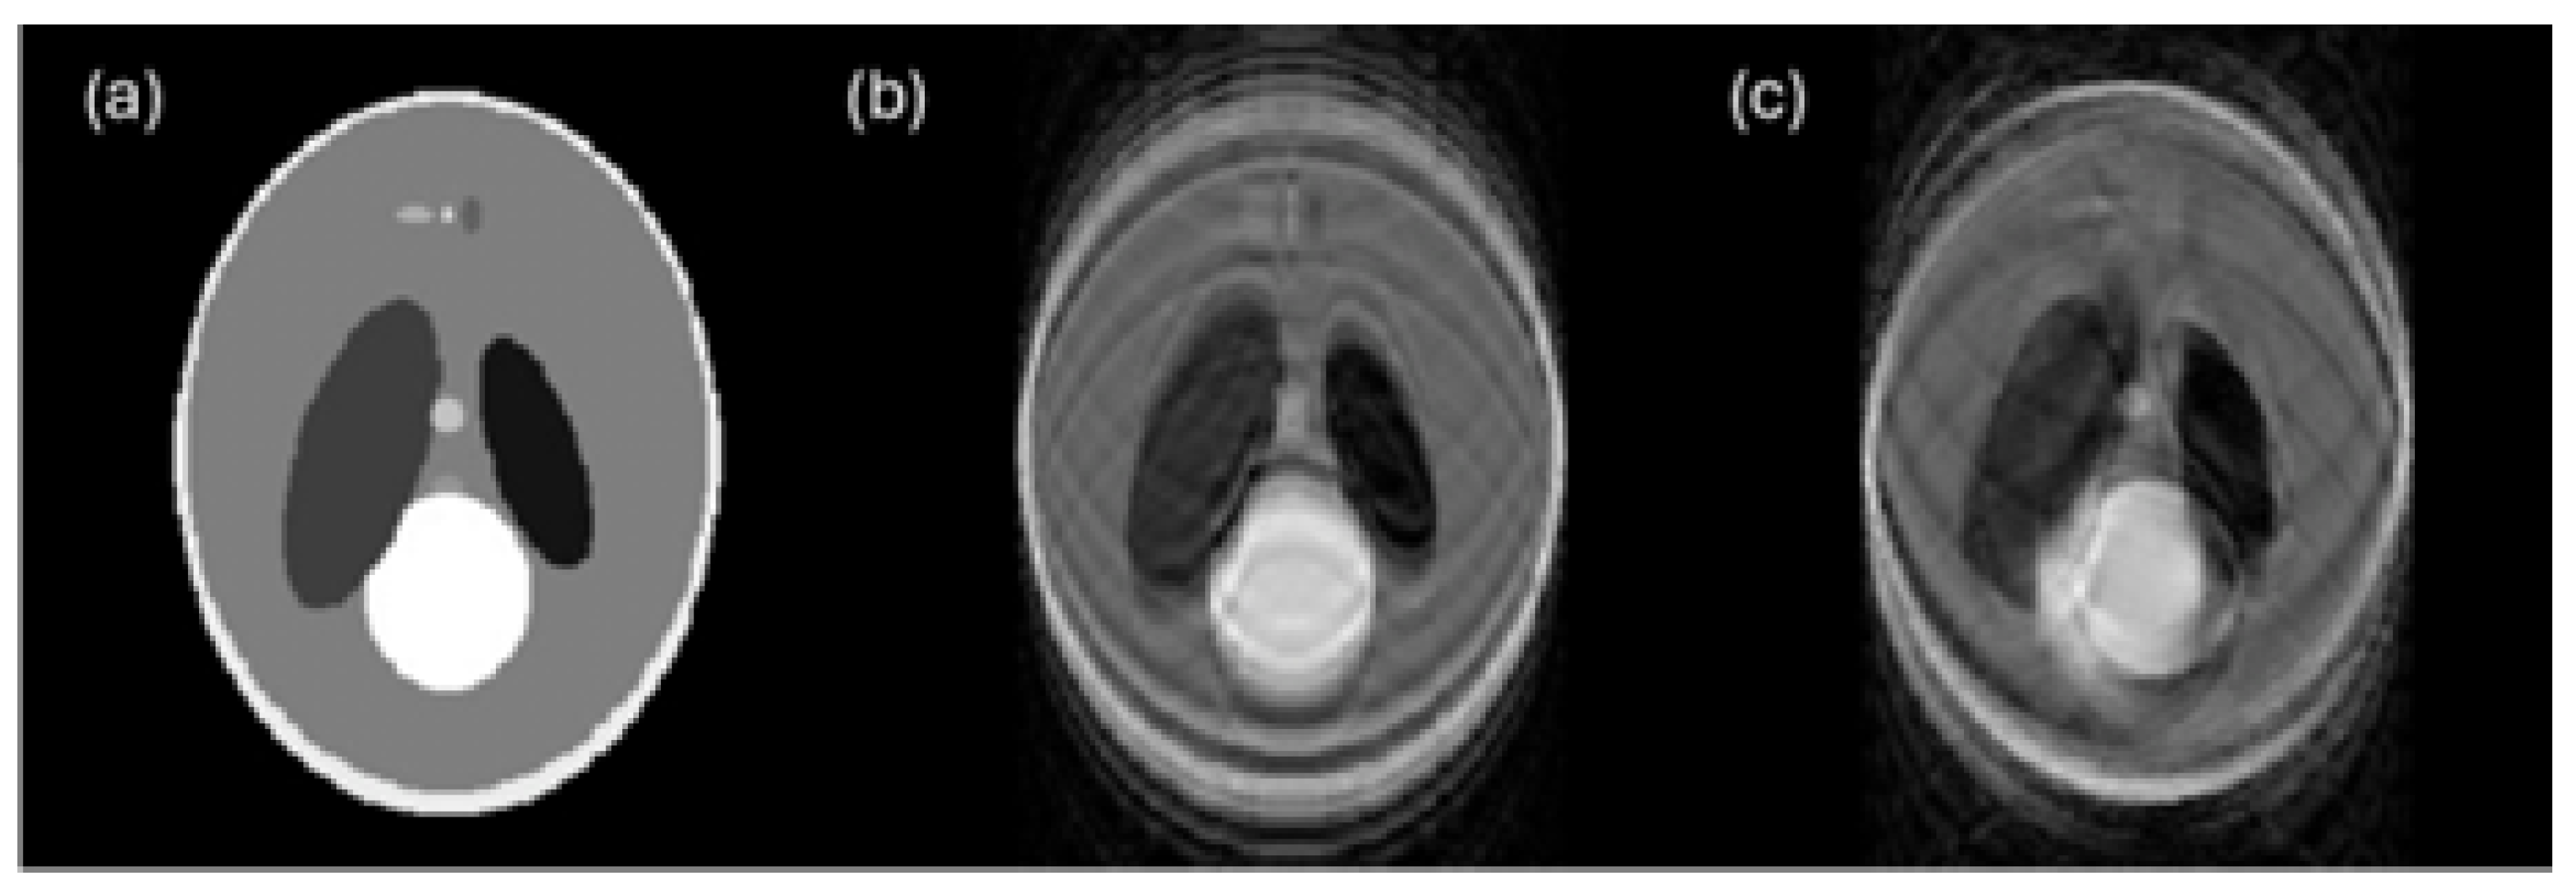

6.3. Noise

6.4. Blur

6.5. Body Habitus/Patient Size

| Blur | CT, MRI, PET | Texture, shape | Loss of edge definition, misclassification |